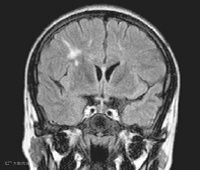

患者,男,17岁,因“反复头痛3年,视物模糊10天”。入院前3年患儿出现反复头痛,不伴发热、咳嗽、抽搐。多次于外院行头颅MRI 显示脑、脊髓、胸髓多发脱髓鞘病变(多处脑组织可见片状不规则异常改变;头颅MRI:颈髓中部可见斑片状异常信号,符合脊髓脱髓鞘病变;颅MRI:脑及胸髓内多发病变)。淋巴细胞亚群示:CD19+20%,CD20+ 17.3%。

左图:头颅MR 示双侧侧脑室旁多个点状、右侧半卵园中心多个片状T2 高信号。右图:头颅MR 示右侧侧脑室顶部多个片状T2 Flare 高信号。